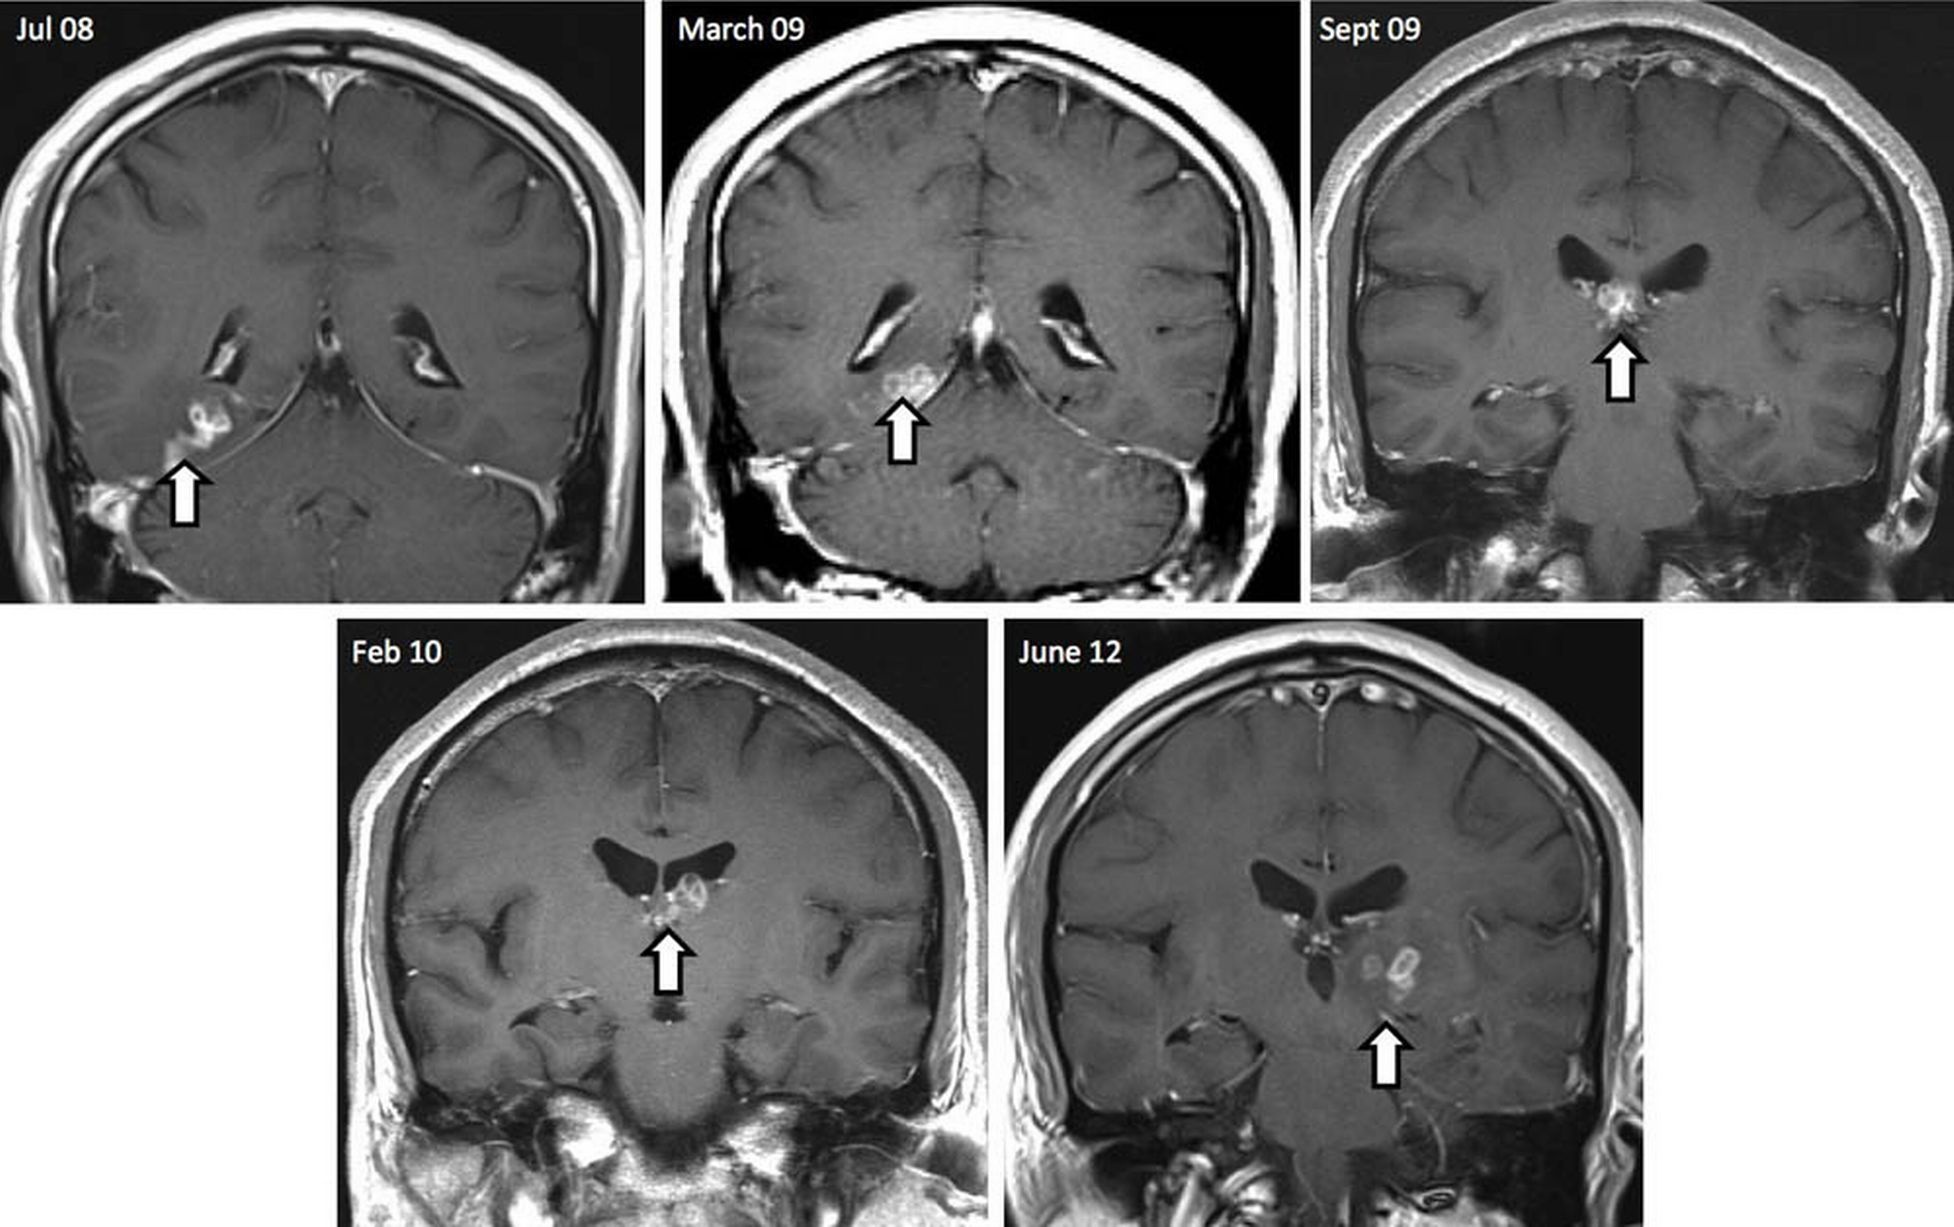

| Vị trí của con sán dây trong não người đàn ông gốc Hoa tại Anh trong loạt ảnh chụp cắt lớp. Ảnh: Mirror |

4 năm sau, người đàn ông trở lại bệnh viện để kiểm tra. Hình ảnh từ máy chụp cắt lớp cho thấy chiều dài của vật thể trong não ông đã lên tới 10 cm. Chuyên gia kết luận vật thể là một con sán dây. Sau đó họ cho ông dùng thuốc để diệt con sán, tạp chí Genome Biology cho hay. Hiện nay sức khỏe của ông đã bình thường.